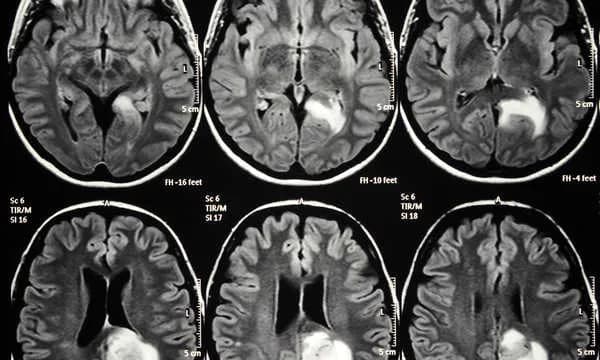

Rezonans magnetyczny (MRI) odgrywa istotną rolę w diagnozowaniu chorób psychicznych, chociaż nie jest narzędziem pozwalającym na bezpośrednie wykrywanie takich schorzeń jak depresja czy schizofrenia. Głównym celem MRI w psychiatrii jest ocena struktur mózgu oraz identyfikacja anatomicznych nieprawidłowości, które mogą wpływać na zdrowie psychiczne pacjenta. Dzięki zaawansowanej technologii, badanie to pozwala na uzyskanie szczegółowych obrazów mózgu, co jest kluczowe w zrozumieniu złożoności zaburzeń psychicznych.MRI jest szczególnie przydatne w sytuacjach, gdy występują nagłe objawy psychotyczne u osób, które wcześniej funkcjonowały normalnie. Badanie to umożliwia wykluczenie organicznych przyczyn tych objawów, takich jak guzy mózgu czy krwiaki. Nieinwazyjność tej metody oraz brak promieniowania rentgenowskiego sprawiają, że jest ona bezpieczna dla pacjentów, co czyni ją idealnym narzędziem w diagnostyce psychiatrycznej.

Rezonans magnetyczny działa na zasadzie wykorzystania silnych pól magnetycznych i fal radiowych, co pozwala na wizualizację struktur mózgu z wyjątkową precyzją. Dzięki temu lekarze mogą dostrzegać nawet drobne zmiany, które mogą być istotne dla diagnozy. Na przykład, MRI może ujawnić zmiany degeneracyjne w mózgu, które mogą wpływać na zachowanie i emocje pacjenta. W psychiatrii, zrozumienie tych struktur jest kluczowe dla postawienia właściwej diagnozy oraz wyboru odpowiedniej terapii.

Rezonans magnetyczny (MRI) jest niezwykle skutecznym narzędziem w identyfikacji strukturalnych zmian mózgu, które mogą mieć istotny wpływ na zdrowie psychiczne. Dzięki zaawansowanej technologii, MRI może wykrywać takie nieprawidłowości jak guzy mózgu, które mogą prowadzić do różnych objawów psychicznych, w tym zmian nastroju i zachowań. Innym przykładem są krwiaki, które mogą występować po urazach głowy i wpływać na funkcjonowanie mózgu. Dodatkowo, MRI pozwala na identyfikację zmian degeneracyjnych, takich jak te obserwowane w chorobie Alzheimera, które mogą prowadzić do pogorszenia pamięci i zdolności poznawczych.Wszystkie te zmiany mają kluczowe znaczenie dla zrozumienia stanu zdrowia psychicznego pacjenta. W przypadku nagłego wystąpienia objawów psychotycznych, MRI może pomóc w wykluczeniu organicznych przyczyn tych objawów, co jest istotne dla dalszego leczenia. Wczesne wykrycie takich nieprawidłowości może znacząco wpłynąć na wybór odpowiedniej terapii i poprawę jakości życia pacjenta.